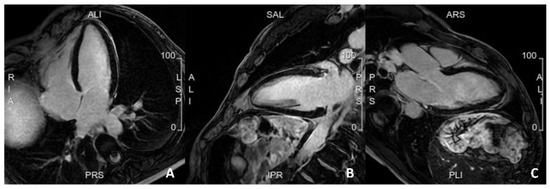

Another imaging technique that may play a prominent role in the future is cardiac magnetic resonance imaging (CMR). Indeed, CMR imaging has become an essential tool in diagnosing and managing cardiovascular diseases. It provides precise information on the structure and function of the heart, including the size and thickness of the heart walls, stroke volume, as well as any abnormalities in the heart muscle [37]. Thus, CMR can be used to detect early signs of myocardial damage or fibrosis, which may indicate an increased risk of heart failure or sudden cardiac death [38] (Figure 2). Consequently, CMR can be used to guide the implantation of an Implantable Cardioverter Defibrillator (ICD) for primary prevention [39]. Additionally, CMR can be used to assess valve function and identify structural abnormalities associated with a higher risk of cardiovascular events [40]. Overall, CMR has the potential to play an important role in primary prevention by providing more accurate risk stratification and guiding personalized management strategies for individuals at increased risk of cardiovascular disease. However, there is a lack of evidence on this topic, and the use of CMR to guide ICD implantation for primary prevention needs to be tested in RCTs. Notably, the ‘Cardiac Magnetic Resonance Guidance of Implantable Cardioverter Defibrillator Implantation in Non-ischemic Dilated Cardiomyopathy (CMR-ICD)’ trial is slated to complete recruitment by November 2023. This study is poised to shed light on the potential benefits of CMR for primary prevention to guide the implantation of ICD. The rationale is that CMR allows a meticulous assessment of cardiac functionality, morphology, and tissue characteristics [41]. The prospect of leveraging CMR, including the evaluation of late gadolinium enhancement (LGE), holds promising implications for enhancing risk stratification and decision-making in this cohort. The feasibility and cost-effectiveness of CMR compared with other imaging modalities also require evaluation.

Figure 2.

A case of a patient with a family history of sudden cardiac death, with frequent but isolated ectopic ventricular beats. Cardiac MRI was completely normal, with no evidence of myocardial fibrosis. (A). 4 Chamber view; (B). 2 Chamber view; (C). 3 Chamber view.